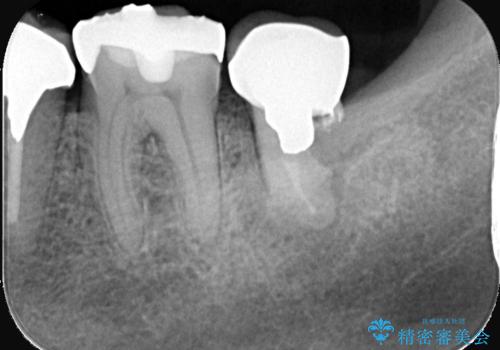

- 過去にヘミセクションが行われていたと思われる左下7番は、大きな歯根嚢胞および根尖病変が認められ、さらに骨縁下カリエスを伴っており、歯肉には瘻孔が形成されている状態でした。

保存は困難と判断し、左下7番は抜歯即時インプラントによる治療を行いました。

また、左下6番には形態が不自然で適合不良のセラミックインレーが装着されていたため、二次カリエスのリスクを考慮し、オールセラミッククラウンによる治療を行いました。